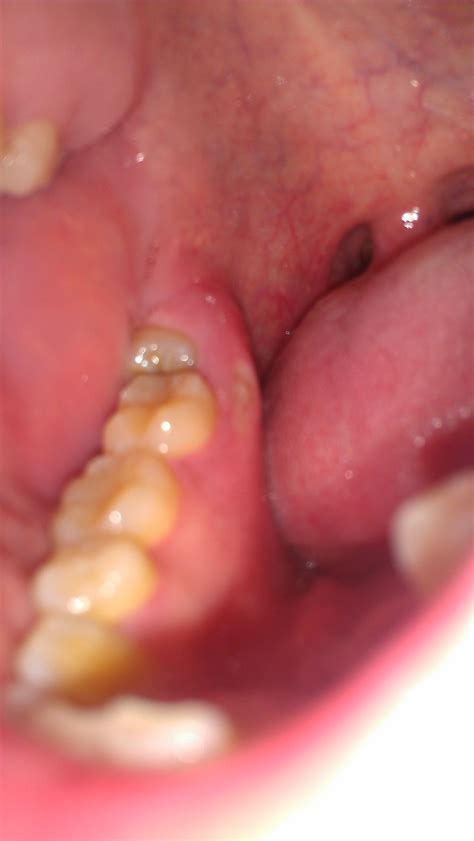

Red Patch On Gums

Oral health is a critical aspect of overall well-being, and one of the most common issues people face is a red patch on gums. This condition can be alarming, but understanding its causes, symptoms, and treatments can help you manage it effectively. This blog post will delve into the various aspects of a red patch on gums, providing you with the information you need to address this issue promptly and effectively.

A red patch on gums can manifest in various forms and intensities. It can range from a small, localized area to a more extensive, inflamed region. The color and texture of the patch can also vary, sometimes appearing smooth or rough, and can be accompanied by pain, swelling, or bleeding. Understanding the underlying causes is the first step in addressing this issue.